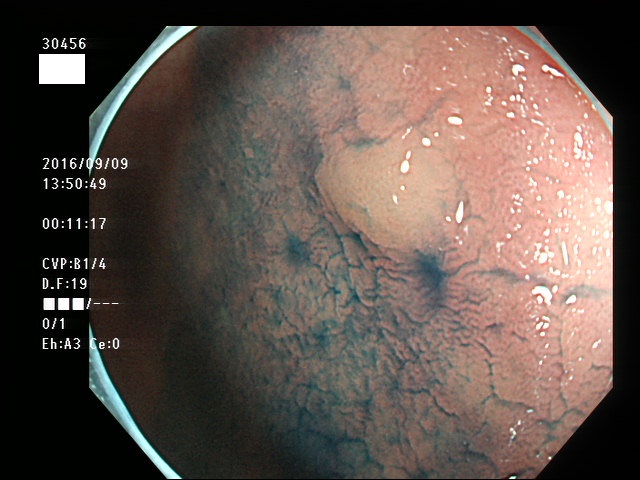

微小カルチノイドの診断

直腸の微小カルチノイドの診断は最も難しい問題です

微小とはいえ、カルチノイドは悪性であり、肛門に近い場所に好発するために、見落とすと数年後には「人工肛門」になる危険があります

進行したカルチノイドの診断は容易なのですが、カルチノイドは「粘膜下腫瘍」と言いまして、は表面が正常粘膜で被われているために微小ですと「単なる過形成結節」「単なる炎症性の隆起」と区別がつかないのです

下記の写真は全て、当院で診断された微小カルチノイド(悪性)ですが、いかに診断が困難かお分かりいただけるでしょう。このような微小病変でさえも見落とせば人工肛門の危険が潜んでいる訳です。